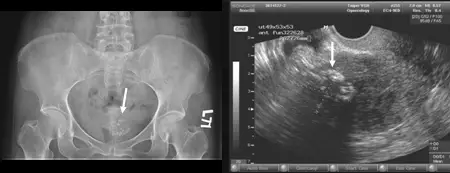

45歲女性病人到醫院做健康檢查,腹部X光片顯示骨盆腔病變如圖示;進一步進行經陰道超音波檢查,結果發現異常如圖示。最可能的診斷為何?

從腹部X光片可見骨盆腔內有一片不規則、呈團塊狀分佈的鈣化(圖中白色箭頭所指),其形態類似爆米花狀鈣化(popcorn calcification),典型見於退行性變性之子宮肌瘤中的鈣化現象 (radiopaedia.org)。超音波影像(經陰道掃描)顯示子宮壁內有一明顯分界的實性腫塊(箭頭所示),腫塊內迴聲多為低迴聲或不均質迴聲,邊緣清楚,可見腫塊後方產生聲影現象,符合leiomyoma的超音波特徵 (pubmed.ncbi.nlm.nih.gov)。